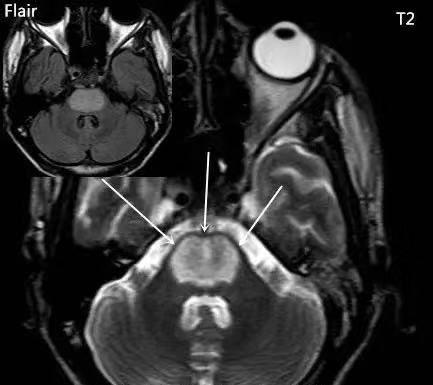

T1 呈低信号,T2 呈高信号,病灶仅累及桥脑中央区,而边缘部分不受累,病灶前方和侧方仅存一薄层脑组织未受累,病灶后缘可延伸到被盖的腹侧。增强后一般无强化,但也可出现强化。

MRI 病变横切位上形态为原形或蝴蝶形,矢状位呈卵圆形,冠状位上呈蝙蝠翼状。